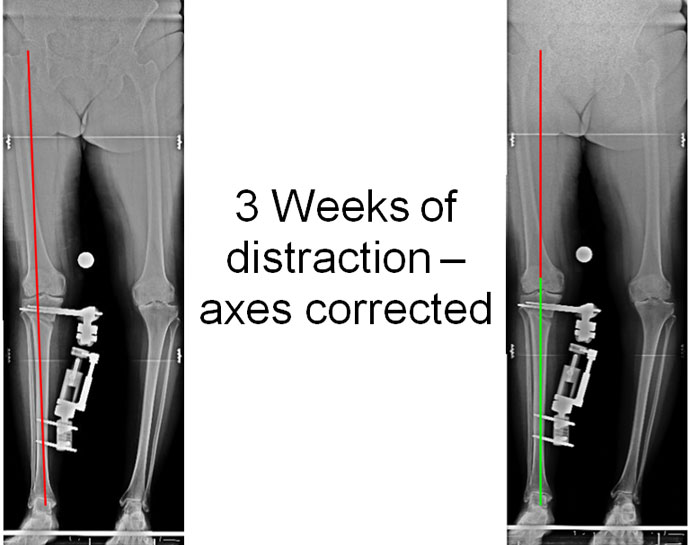

| 3 Weeks of distraction – axes corrected |

| At the end of 3 weeks of distraction the correction is completed and angles are confirmed by the full length x-ray. The load bearing axis is now passing through the center of the knee joint as opposed to the inner side before surgery. |